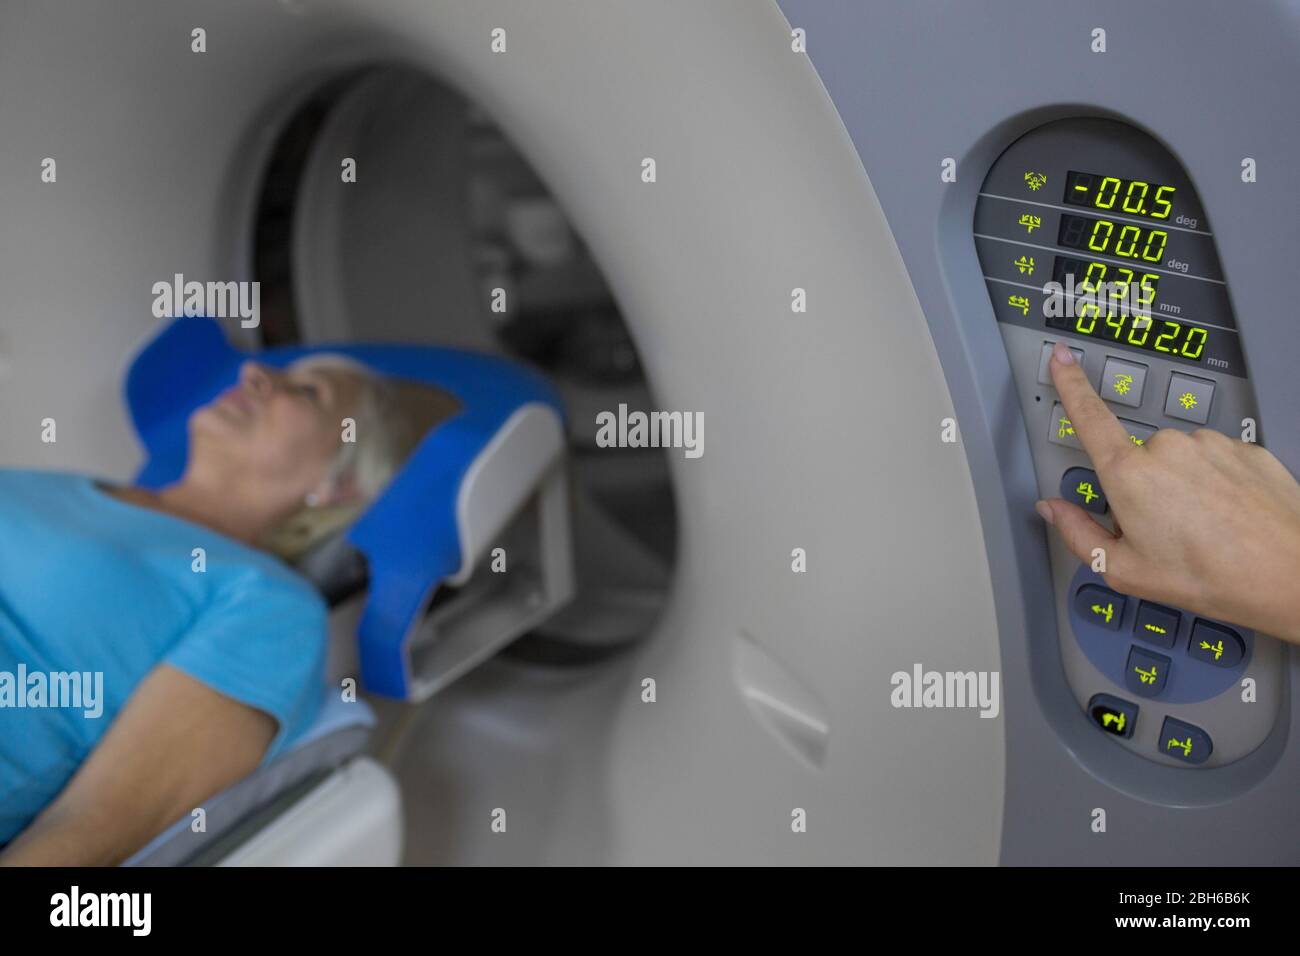

Senior patient at a computer tomography exam Stock Photohttps://www.alamy.com/image-license-details/?v=1https://www.alamy.com/senior-patient-at-a-computer-tomography-exam-image354797035.html

Senior patient at a computer tomography exam Stock Photohttps://www.alamy.com/image-license-details/?v=1https://www.alamy.com/senior-patient-at-a-computer-tomography-exam-image354797035.htmlRF2BH6B6K–Senior patient at a computer tomography exam